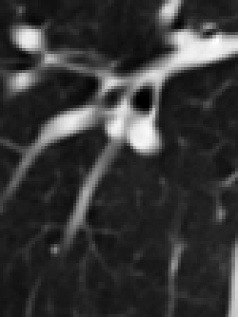

(a) original slice (b) original transform (c) mesh-based compensation (d) block-based compensation

(blurred) (sharp) (more details)

For visual comparison of the lowpass bands of the different approaches, a zoom into one slice of the lowpass band of thorax2 is shown in Figure 2. Compared to the corresponding original slice in Figure 2 (a) the blurriness of the lowpass band of the original transform can be seen in Figure 2 (b). The lowpass bands of the compensated transforms in Figure 2 (c) and (d) represent the structures sharper and more detailed.